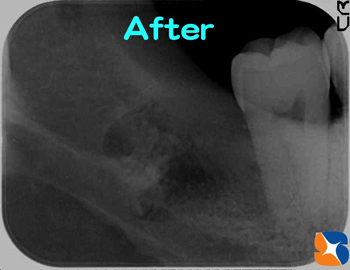

〈抜歯前〉この画像だけでは、下あごの骨の太い神経と智歯が交差しているように見えます。土曜日にしか手術が出来ないこの患者様は、

何処の医院へ行っても断られたそうです。

〈抜歯後〉CTの力を借りて、無事に抜歯が終了。抜歯後2週間は、腫れと痛みを訴えておられました。当院で必ず使用する抜歯後のテルプラグは、無料で使用しております。

歯の根を2分割にして抜歯しました。根の先が曲がって凸起していたため、引っ掛りが強く、より難しい抜歯となりました。現在、定期検診で歯石取りにも来られていますが、腫れや痛みは全く消失したとのこと。